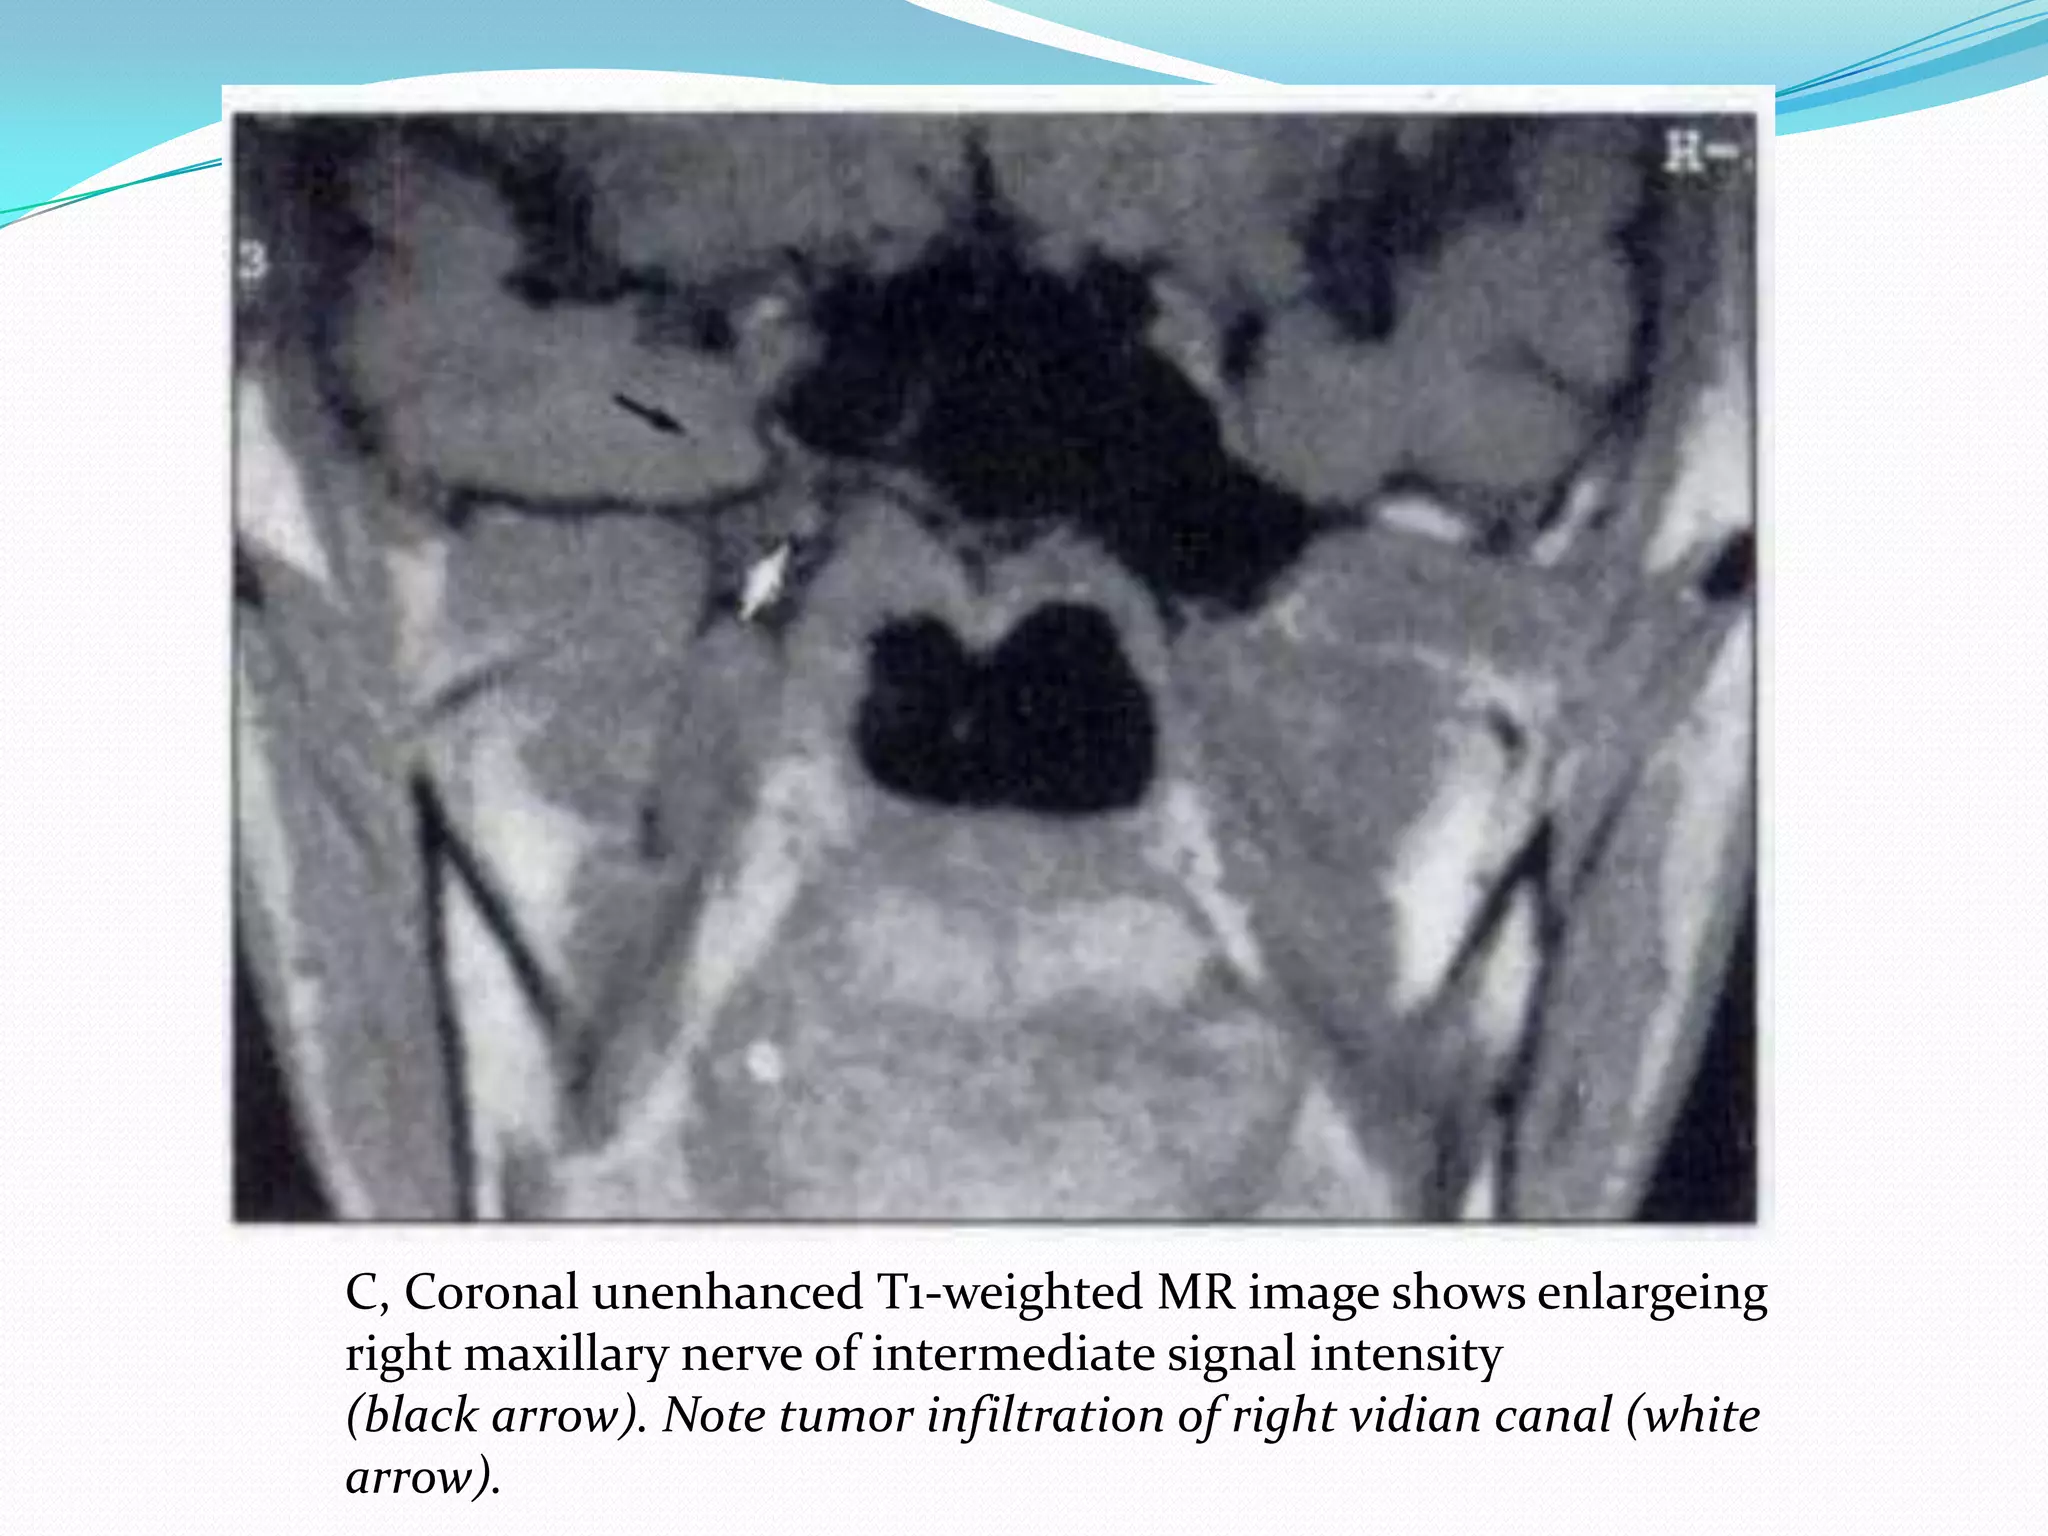

C, Coronal unenhanced T1-weighted MR image shows enlargeing

right maxillary nerve of intermediate signal intensity

(black arrow). Note tumor infiltration of right vidian canal (white

arrow).